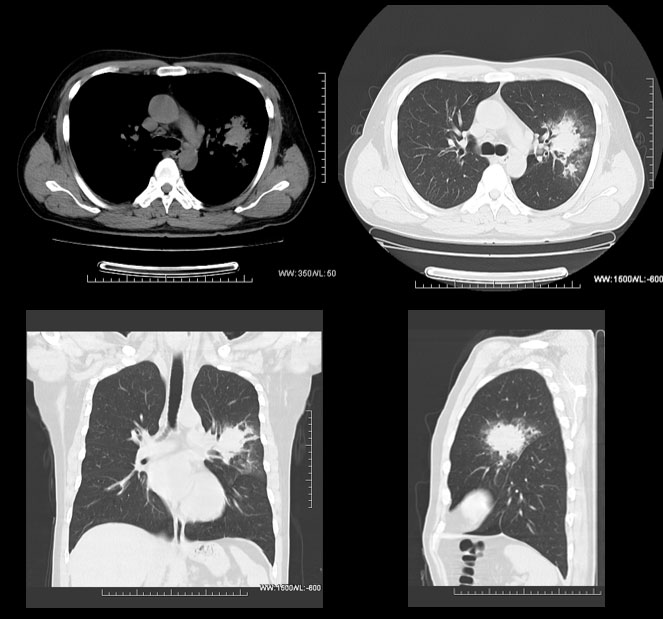

症例名:肺がんを見つけた症例

症例コメント:数カ月間痰が続き、体重も減少してきたため精査目的で受診された40歳代男性症例。

左上葉に腫瘤を認め、縦隔リンパ節も腫大しており、専門機関に紹介。肺癌疑いで精査加療を行ってもらっている。

CT検査により迅速な治療に移行できた症例。

撮影条件 1sec/rot HP1.75 200mA ASiR30%

撮影時間 10.43秒